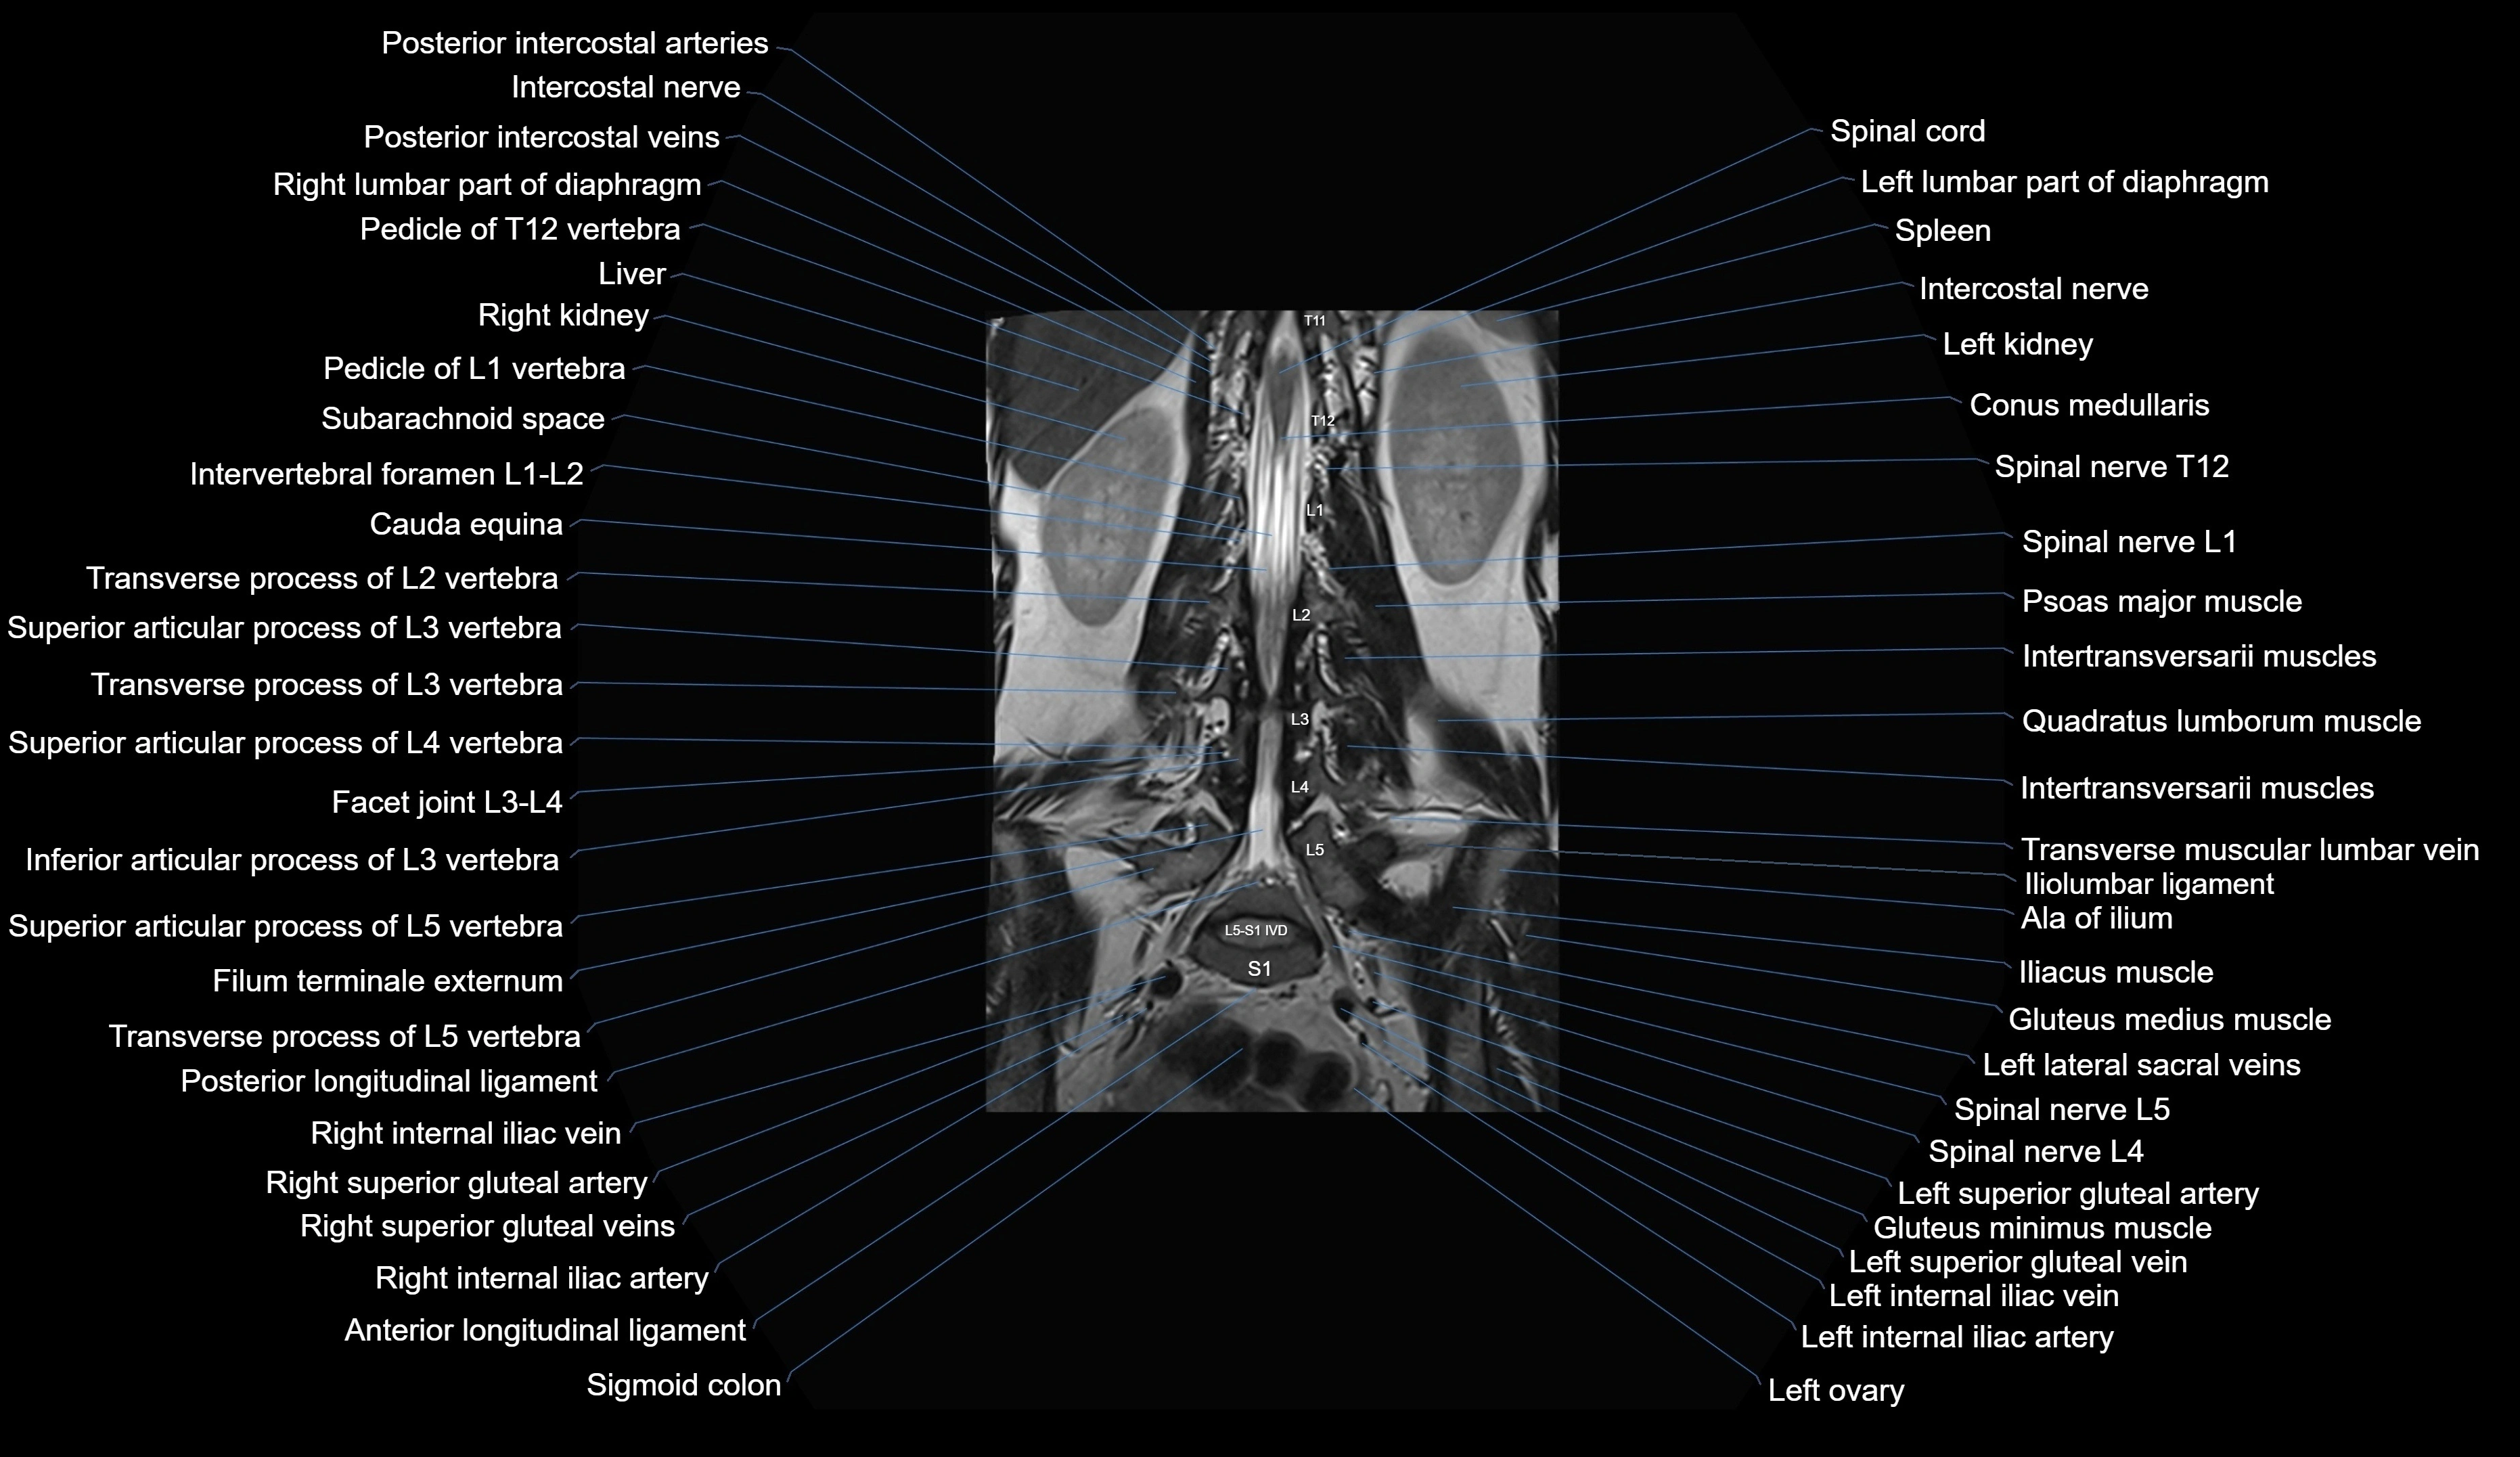

MRI images